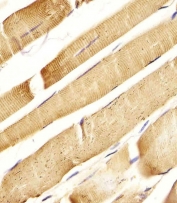

IHC testing of FFPE human skeletal muscle tissue with CD130 antibody. HIER: steam section in pH6 citrate buffer for 20 min and allow to cool prior to staining.